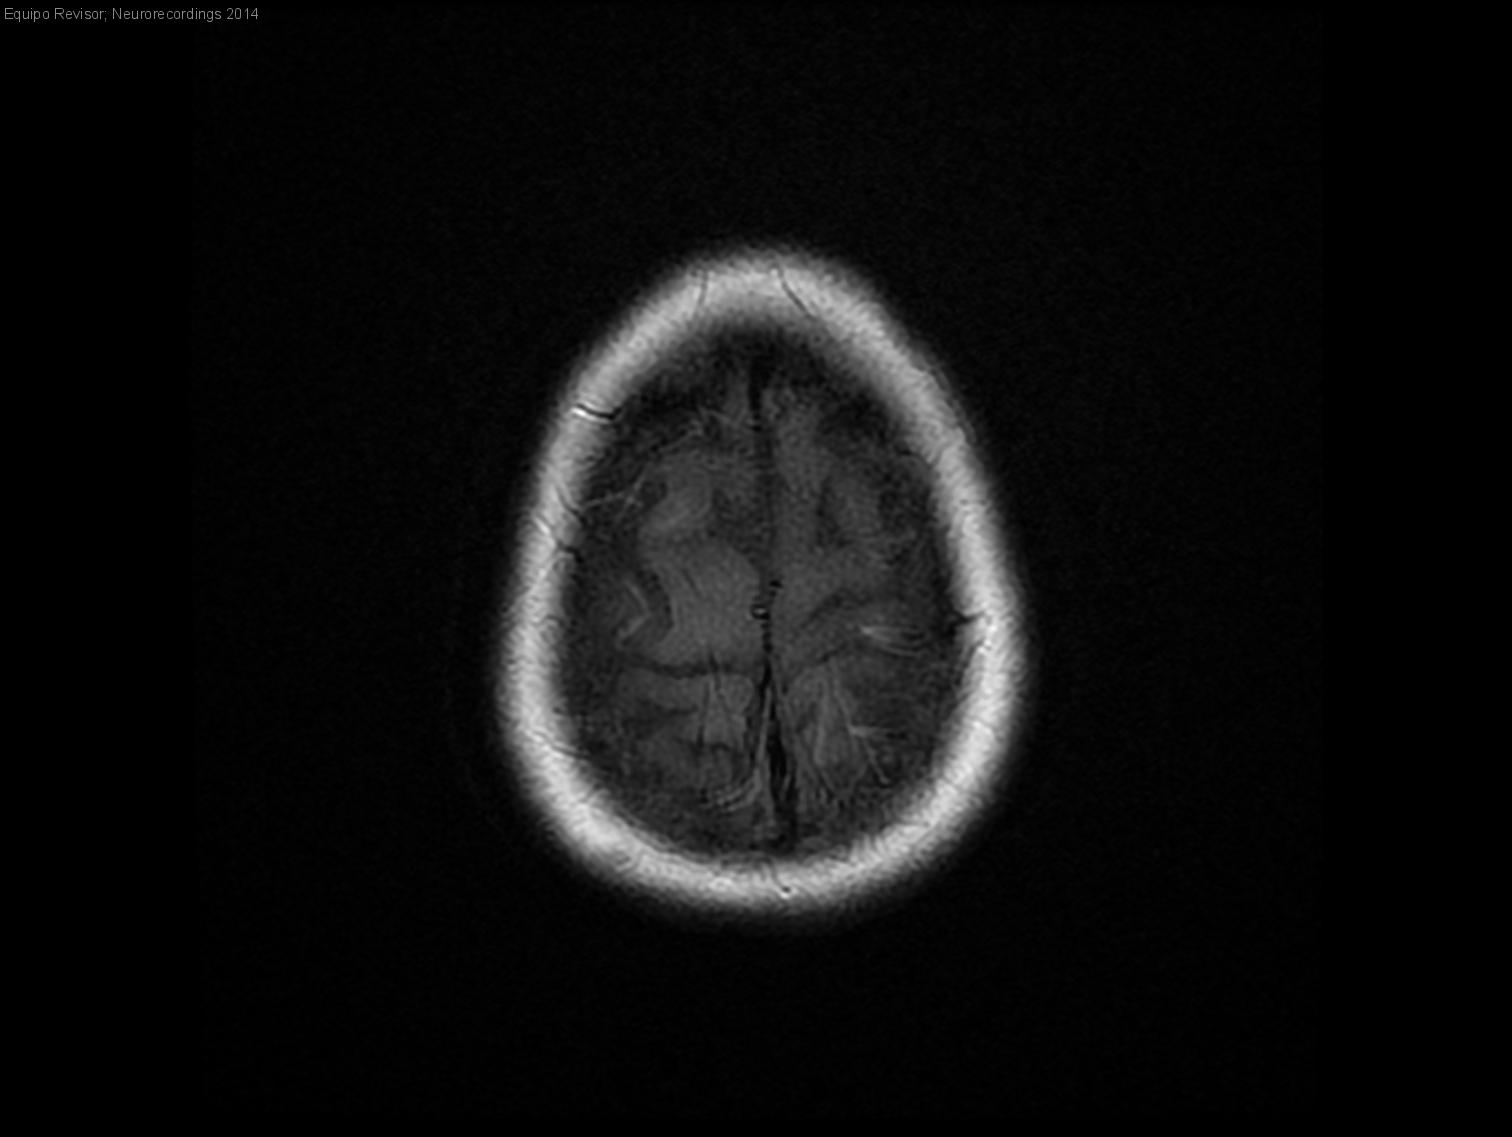

Mujer | 46 años

Diagnóstico final: Esclerosis tuberosa. Epilepsia refractaria

Neurología: Epilepsia | Neurooncología

Etiología: Neoplasias | Genético / idiopático